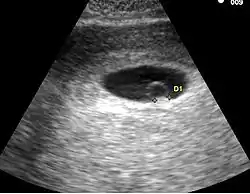

Visualisation d'un sac ovulaire sans vésicule vitelline ou embryon

Dans ce cas, seuls les trois mêmes diagnostics suivants sont possibles :

• La grossesse est évolutive mais moins avancée

• La grossesse est arrêtée

• Il s'agit d'un pseudo-sac gestationnel (œuf clair) avec une grossesse extra-utérine